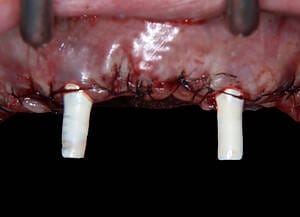

Natalie’s treatment began with a comprehensive clinical assessment, including a review of her medical and dental history, a full examination, and analysis of her functional difficulties such as her tongue habit and altered bite. A 3D cone-beam CT scan was then taken to assess bone quality and volume, identify areas of infection, and map important anatomical structures to ensure safe implant placement.

All data were transferred into digital treatment planning software, allowing virtual placement of implants and collaboration with the dental laboratory before surgery. This enabled careful evaluation of long-term outcomes and ensured the design of provisional and final prosthetics could be completed with precision. Following these discussions, the decision was made to proceed with the Fixed-Teeth-in-a-Day approach using the All-on-4 technique.

Surgical phase